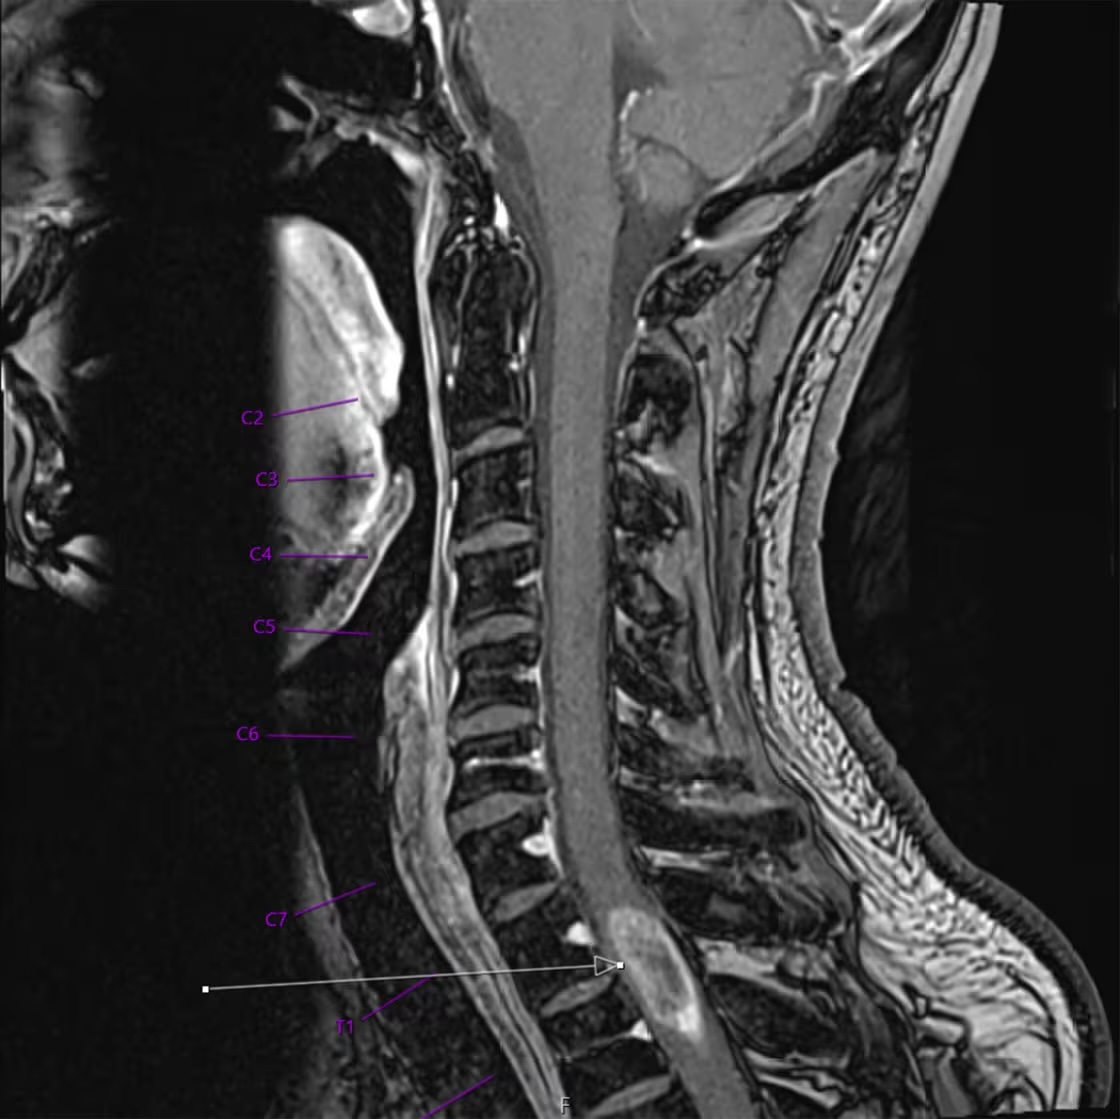

The result was startling: The scan revealed a large tumor lurking inside his spine, not far from the base of his neck.

An arrow points to the large tumor in Loutzenhiser’s spine, near the base of his neck. Courtesy WashU Medicine